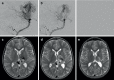

Background: Adenosine induced cardiac standstill has been used intraoperatively for both aneurysm and arteriovenous malformation (AVM) surgery and embolization. We sought to report the results of adenosine induced cardiac standstill as an adjunct to endovascular embolization of brain AVMs.

Results: We identified 47 patients (22 female, 47%) with average age 42 ± 17 years (range 6-77 years) who had undergone AVM embolization procedures using adjunctive circulatory standstill with adenosine. In total there were 4 Spetzler Martin grade 1 (9%), 9 grade 2 (18%), 15 grade 3 (32%), 8 grade 4 (18%), and 11 grade 5 (23%) lesions. Of the AVMs six were ruptured or had previously ruptured. The average number of embolization procedures per patient was 5.7 ± 7.6 (range 1-37) with an average of 2.6 ± 2.2 (range 1-14) embolization procedures using adenosine. Overall morbidity was 17% (n = 8/47) and mortality 2.1% (n = 1/47), with permanent morbidity seen in 10.6% (n = 5/47) postembolization. Angiographic follow-up was available for 32 patients with no residual shunt seen in 26 (81%) and residual shunts seen in 6 patients (19%). The angiographic follow-up is still pending in 14 patients. At last follow-up 93.5% of patients were mRS ≤2 (n = 43/46).

Conclusion: Adenosine induced cardiac standstill represents a viable treatment strategy in high flow AVMs or AV shunts that carries a low risk of mortality and permanent neurological deficits.